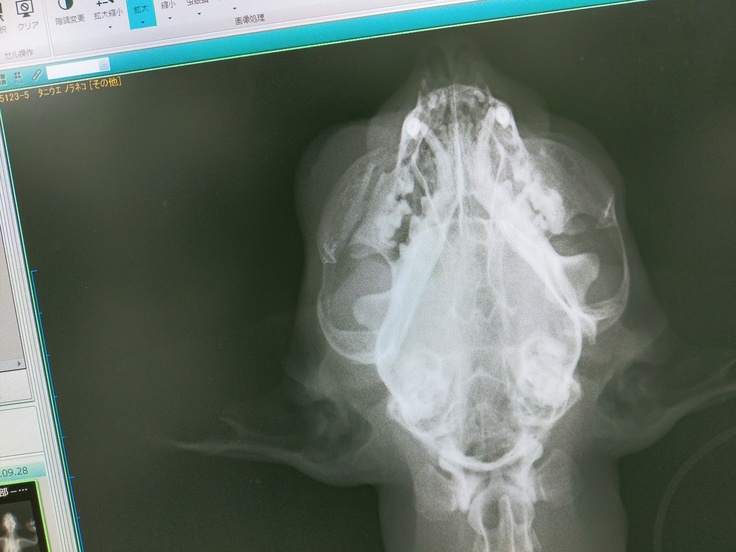

先日、会社の帰り道で事故にあった猫を保護しました。田舎道なのですが裏道としてトラックやダンプも利用する交通量の多い道です。猫やたぬきもよく亡くなっています。当時少し渋滞していたので亡くなった動物を避けているのかと思い目をやると、やはりはねられた猫がいました。まだ動いていたので車を脇に寄せブランケットを持って走りました。対向車に停まってもらい猫を保護。呼吸は浅く顔は血まみれ。その足で動物病院へ走りました。胴体に損傷はみられませんでしたが左上顎骨折、鼻の骨が割れており出血は鼻と口からでした。

[左頬骨折レントゲン]

頭を打っているようなのですが病院にCTがなく脳の損傷は不明で容態が安定しないため入院しての経過観察となっています。外傷は上顎の骨折、鼻の骨が割れており左眼の瞳孔が開いています。酸素室に入り今のところ手術は必要ないとのことですが、口が開けずごはんが食べられないようであれば首からチューブを通す予定です。